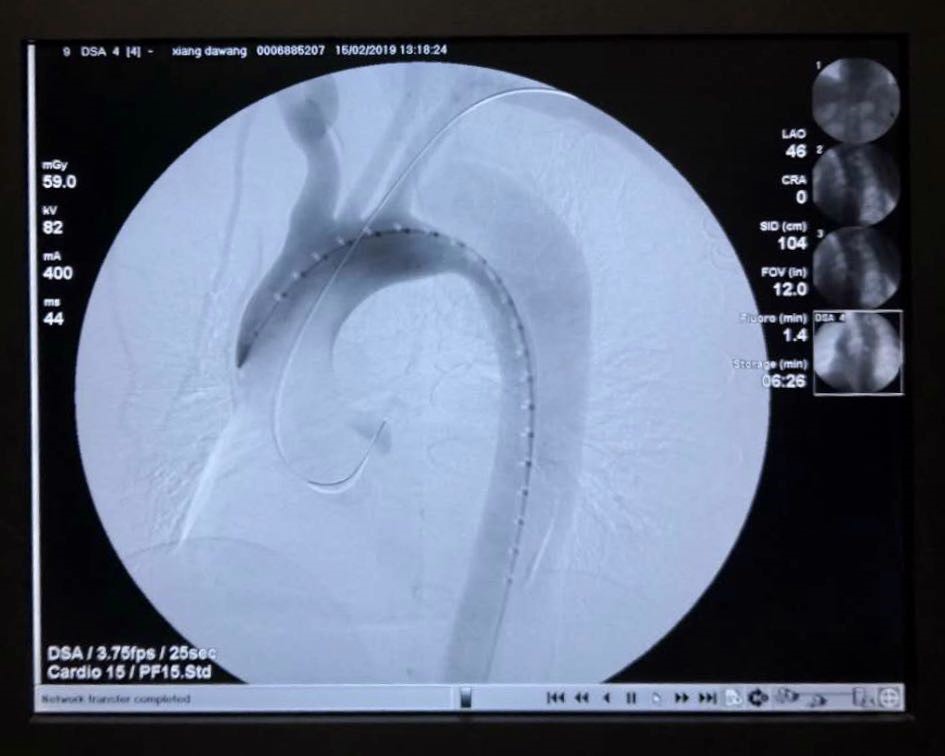

术中通过DSA造影显示:主动脉夹层破口位于左锁骨下动脉近端,真腔压闭!舒畅教授为患者完美的实施TEVAR+左锁骨下动脉裙边烟囱支架置入术,手术过程非常顺利,胸主动脉支架释放良好,患者的主动脉夹层破口封闭良好,真腔打开良好,左锁骨下动脉释放的裙边支架血流通畅,没有内漏发生。

术前DSA

术后DSA